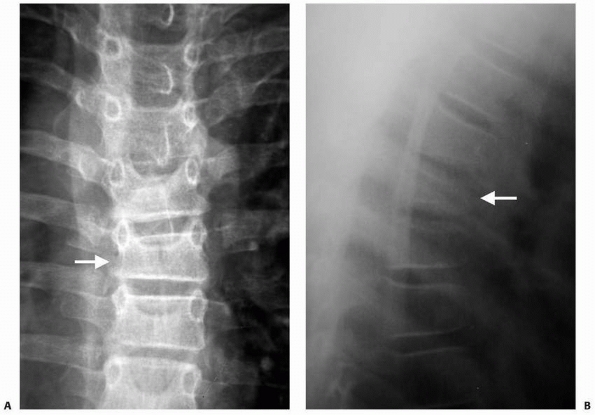

![]() |

FIGURE 19-3 Denis classification of thoracolumbar fractures. A.

Compression fracture: This injury results in mild wedging of the vertebra primarily involving the anterior aspects of the vertebral body. The posterior vertebral height and posterior cortex remain intact. B. Burst fracture: A burst fracture involves both the anterior and middle columns with loss of height throughout the vertebral body. There may be substantial retropulsion of the posterior aspect of the vertebra into the spinal canal. In addition, posterior vertebral fractures and/or ligamentous injury may occur. C. Flexion distraction injuries: This fracture, which occurs commonly with a seatbelt injury mechanism, results in posterior distraction with disruption of the ligaments and bony elements of the posterior column, commonly extending into the anterior columns with or without compression of the most anterior aspects of the vertebra. D. Fracture dislocation: These complex injuries involve marked translation of one vertebra on another with frequently associated SCI as a result of translations through the spinal canal. |